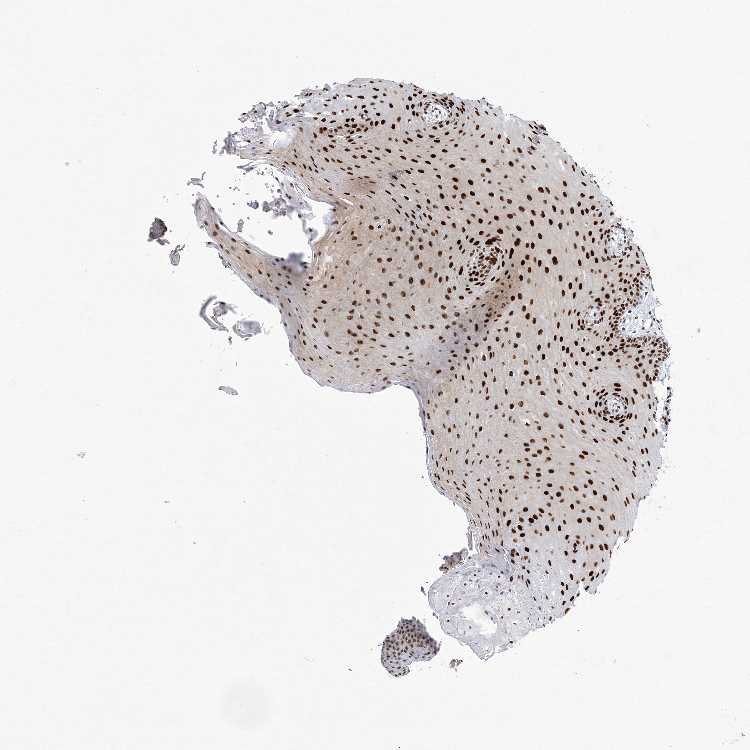

TISSUE PRIMARY DATA ORAL MUCOSA Show tissue menu

Oral mucosa

ORAL MUCOSA - Antibody stainingi

Antibody staining in the annotated cell types in the current human tissue is reported as not detected, low, medium, or high, based on conventional immunohistochemistry profiling in selected tissues. This score is based on the combination of the staining intensity and fraction of stained cells.

Each image is clickable and will lead to virtual microscopy that enables deeper exploration of all samples and also displays staining intensity scores, fraction scores and subcellular localization as well as patient and tissue information for each sample.

Antibody HPA046387Antibody CAB037214Antibody CAB037285

Squamous epithelial cells HighHighHigh